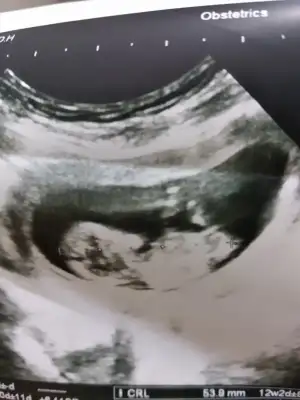

dr soylemeden siz gorun genital nub teorisi ( bebegin cinsiyeti)

Usg net degil ama Erkek gibi sankiİyi akşamlar kızlar. 11+6 haftaligiz. Bizde yorum alabir miyiz :)

Başka usg varmı nub göremedim kafa yapısı erkek gibi tutmayada bilirİyi akşamlar kızlar. 11+6 haftaligiz. Bizde yorum alabir miyiz :)

Merhaba arkadaşlar.Bize de yorum yapabilirseniz çok seviniriz 11+6 günlük

11+6 günlük

Usg ler net degil net olmamakla birlikte kız diyorumMerhaba arkadaşlar.Bize de yorum yapabilirseniz çok seviniriz11+6 günlük

Ayy kız bu Bebiş benceMerhaba arkadaşlar.Bize de yorum yapabilirseniz çok seviniriz11+6 günlük

Kafa yapısına göre erkek ama tutmaya bilir nub görünmüyor 11 yada 12 hafta varsa tahmin ederimMerhaba hanımlar

Erkek tam net degil usg başka varmı netleştirim tahminim şimdilik erkek diyorum ve kaç haftalıkMerhaba bu ultrason görüntüsü bir akrabamin yorumunuzu bekliyorum :)